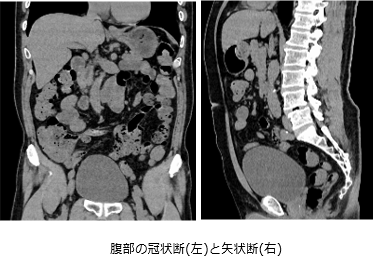

CT22.png CT23.png

いろいろな断面を撮影することができるため、

骨や臓器などの状態を詳しく見る事ができます。

造影剤を使用することで、臓器や血管の構造などを

より詳細に把握することができます。